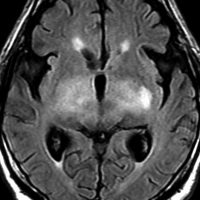

MRI画像所見 60代で嚥下障害と構音障害で発症した例

延髄から中脳まで腫瘍があって脳幹部が腫れています。この画像ですと,小児のびまん性橋膠腫(DIPG,びまん性正中グリオーマ)のように見えます

両側視床から大脳基底核,両側大脳半球深部白質,脳梁まで広範囲に腫瘍が存在します。退形成性星細胞腫のようにまだらにガドリニウム増強されます。